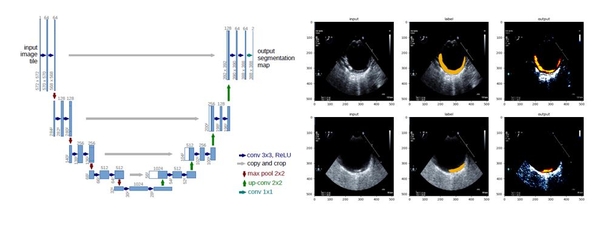

연구팀은 머신러닝의 다양한 기법 중 오토엔코더(Autoencoder)와 유넷(U-net)모델을 대동맥벽의 초음파 영상 판별에 적용했다. 대동맥벽을 초음파 영상으로 판별하면 뇌졸중의 원인으로 떠오르고 있는 대동맥 동맥경화성 플라크의 상태를 확인할 수 있다.

머신러닝을 의료 분야에 활용하기 위한 시도는 다양하게 있었지만, 대동맥 플라크(Plaque) 상태에 따라 분류하고, 플라크의 두께 측정에 적용할 수 있는 딥러닝 모델 개발은 새로운 시도다.